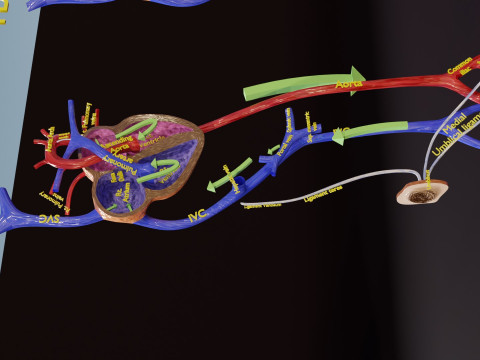

The model meshes include adult circulation versus circulation in Tetralogy of Fallot (TAF), arrow labels and text labels. The blood flow in a patient with Tetralogy of Fallot is outlined in this model. To contrast it to normal blood circulation a separate model of normal circulation is included. The Tetralogy of Fallot (OVER RIDING OF AORTA, PUL STENOSIS, VENTRICULAR SEPTAL DEFECT, RIGHT VENTRICULAR HYPERTROPHY), fossa, ligament teres , venosus, and arteriosus are duly depicted with proper labelling and blood flow directional arrows. Excellent model for teaching, demonstration and knowlegde of human body. The models include both procedural and image textures blend files separately. The texture file include diffuse, roughness and normal png and jpeg based on non overlapping UV maps.